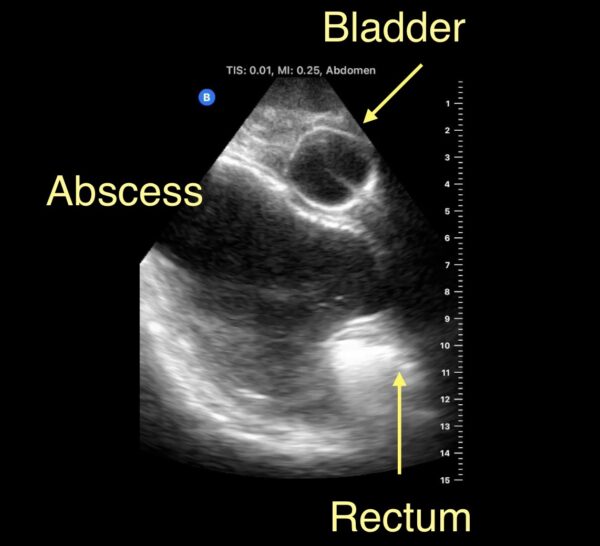

Transrectal Drainage

Dr. Haun uses ultrasound to guide a transrectal drainage procedure to avoid a major operation.